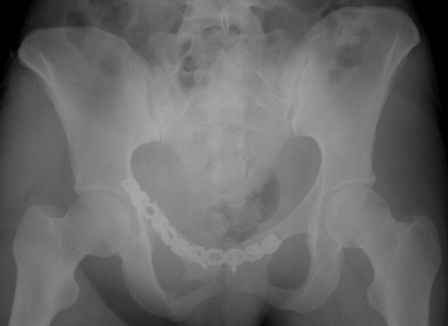

Ротационно-нестабильное повреждение.Наверняка есть перелом крестца слева.Нужно сделать проекцию хотя бы inlet.А в принципе можно скомбинировать, пластину на лоно + аппарат.

думаю, для начала необходимо определиться с типом перелома. Для этого, как минимум необходима проекция inlet, дальше часть вопросов может отпасть сама-собой.

Конечно важен механизм травмы, на первый взгляд возможно двустороннее повреждение задних отделов.

Больную нужно дообследовать- inlet, outlet, боковые проекции таза 3/4, КТ таза, таз 3D.

Уважаемые коллеги!

Спасибо за полезные советы! По inlet и outlet обнаружили перелом крестцас той-же стороны. Сегодня прооперировали реконструктивной пластиной с перекрытием симфиза, крестец, увы, фиксировать было нечем - оставили так (тем более, что грубой дислокации там нет). Рентгенограммы выложу позже.